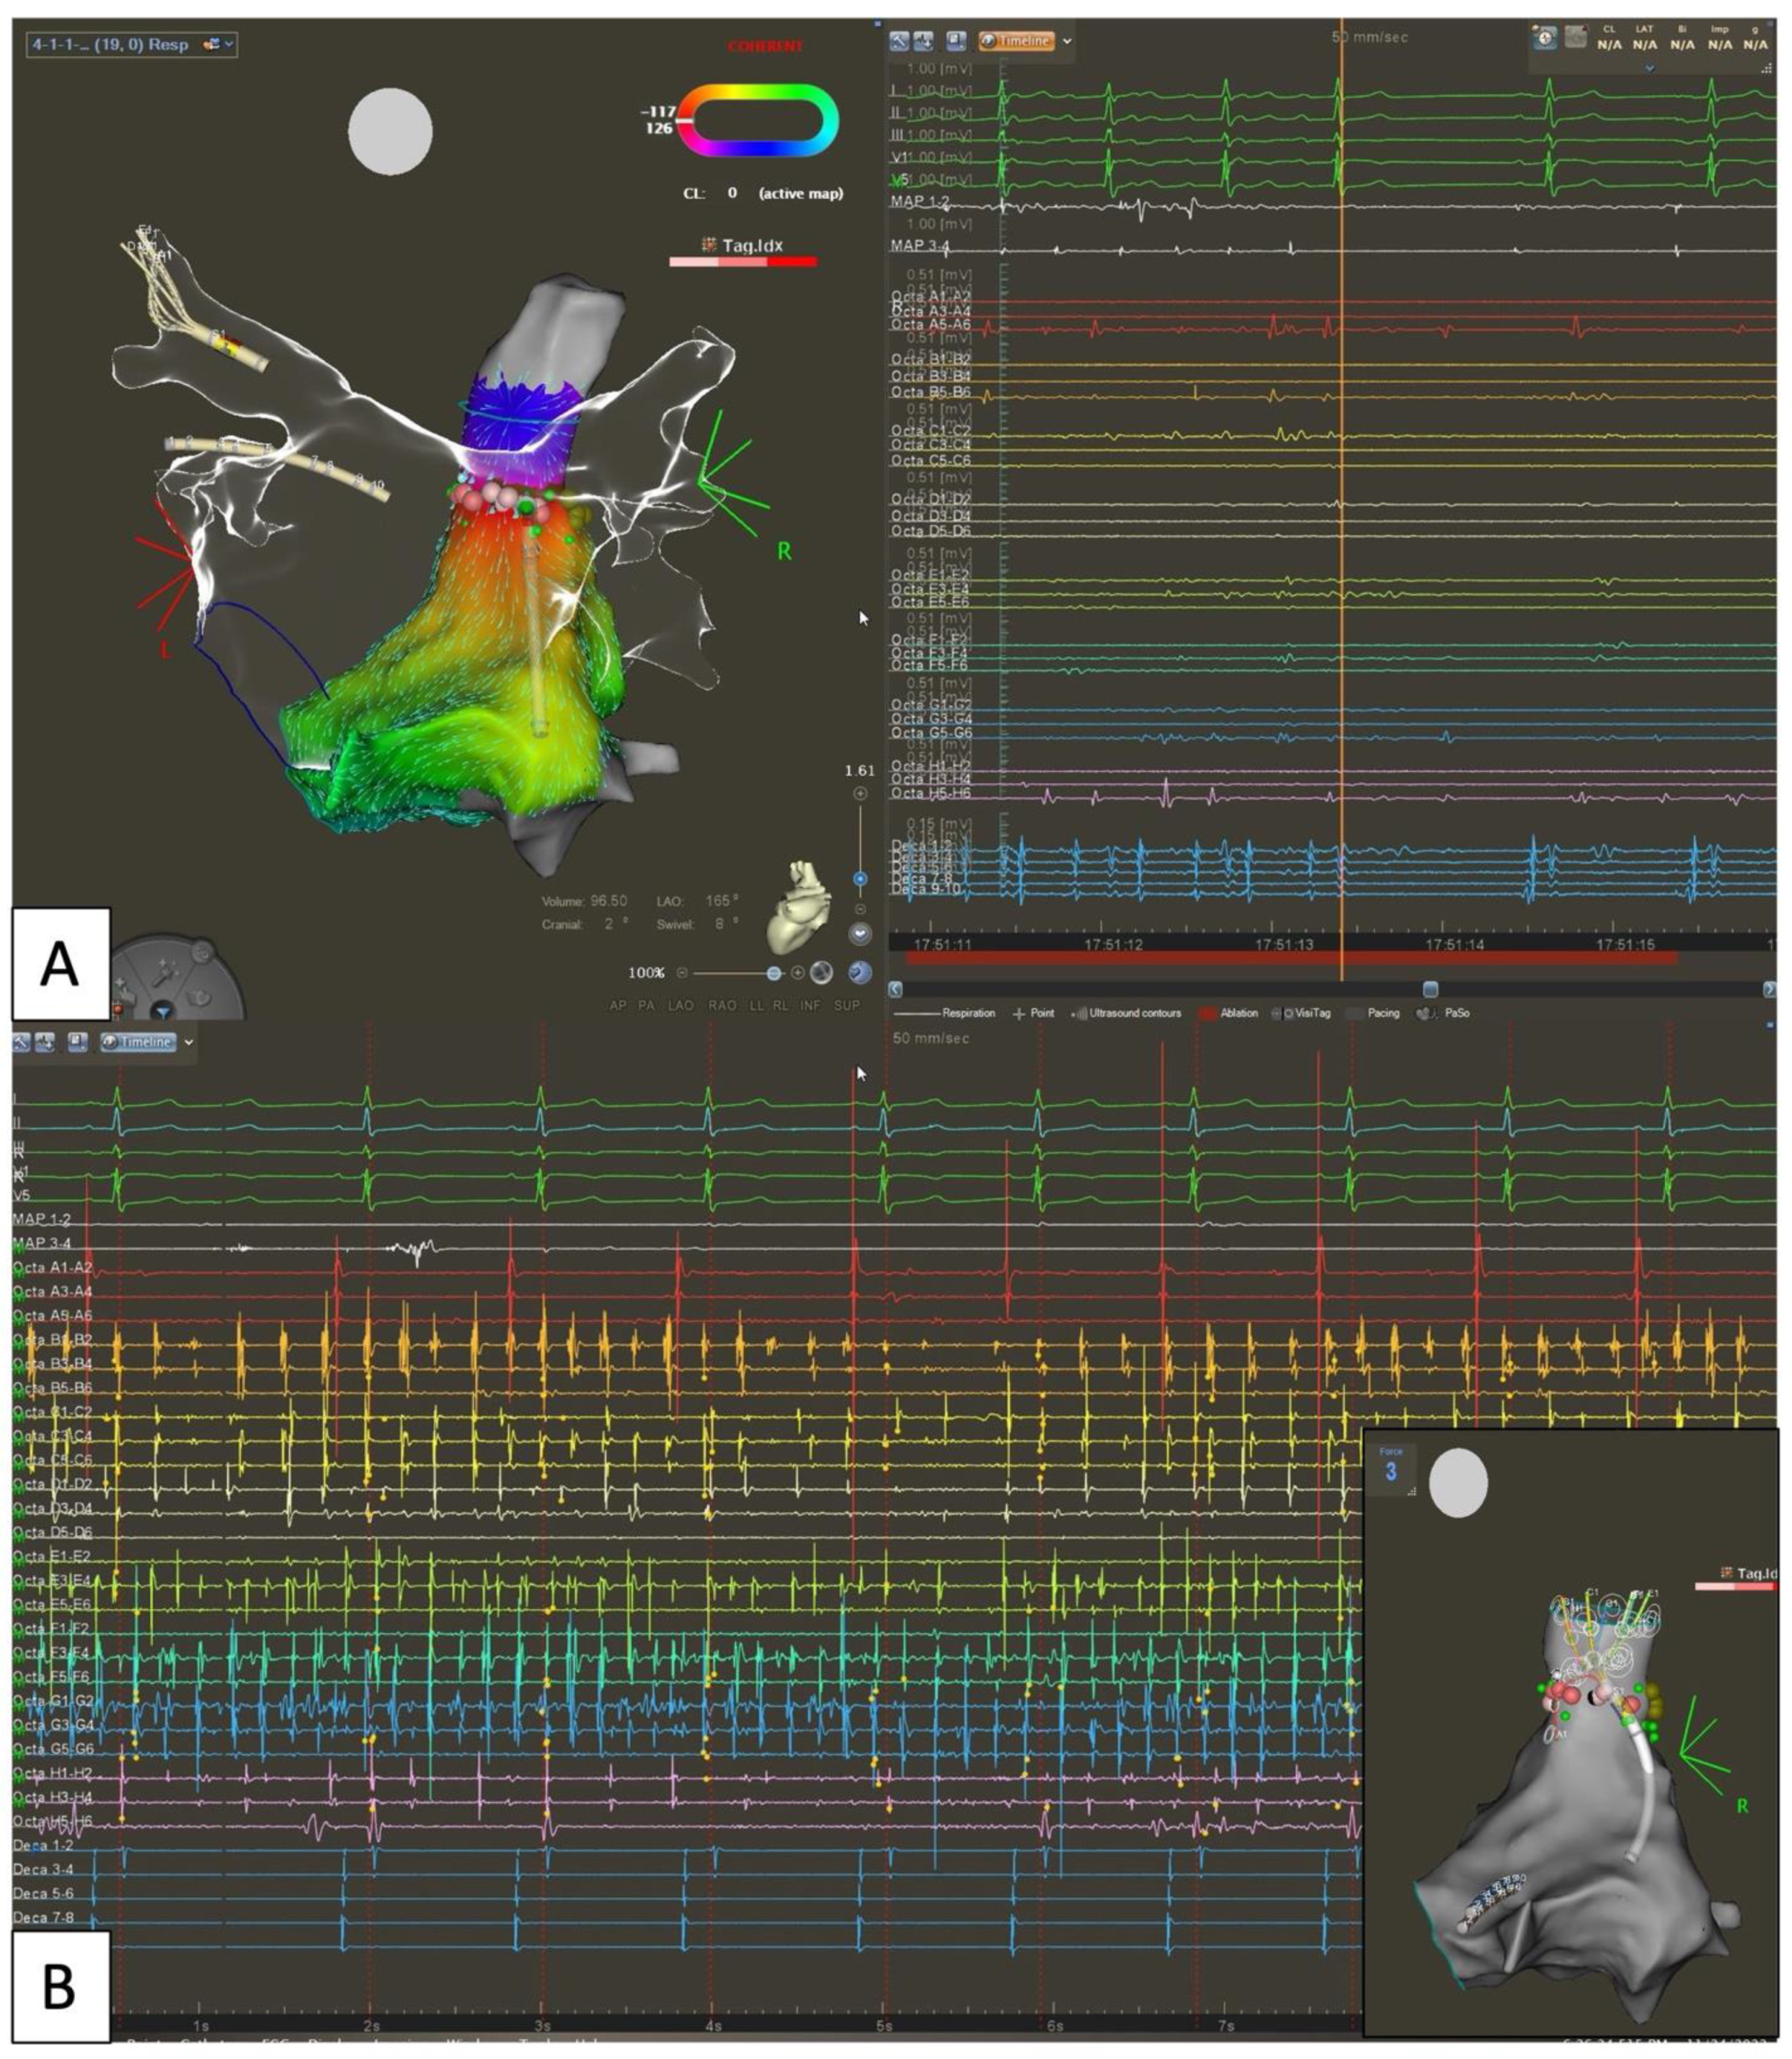

5.3. Empirical Anatomical “Compartmentalization” (Cox-Maze-like Strategy) and Role of Epicardial Connections

- Knecht, S.; Hocini, M.; Wright, M.; Lellouche, N.; O’Neill, M.D.; Matsuo, S.; Nault, I.; Chauhan, V.S.; Makati, K.J.; Bevilacqua, M.; et al. Left Atrial Linear Lesions Are Required for Successful Treatment of Persistent Atrial Fibrillation. Eur. Heart J. 2008, 29, 2359–2366. [Google Scholar] [CrossRef]

- Madaffari, A.; Knecht, S.; Spies, F.; Schaer, B.; Kühne, M.; Sticherling, C.; Osswald, S. Epicardial Connection: The Achilles Heel of Gap Mapping After Wide Antral Pulmonary Veins Isolation. JACC Clin. Electrophysiol. 2019, 5, 1356–1357. [Google Scholar] [CrossRef] [PubMed]

- Pambrun, T.; Derval, N.; Duchateau, J.; Denis, A.; Chauvel, R.; Tixier, R.; Welte, N.; André, C.; Nakashima, T.; Nakatani, Y.; et al. Epicardial Course of the Musculature Related to the Great Cardiac Vein: Anatomical Considerations and Clinical Implications for Mitral Isthmus Block after Vein of Marshall Ethanol Infusion. Heart Rhythm 2021, 18, 1951–1958. [Google Scholar] [CrossRef] [PubMed]

- Derval, N.; Duchateau, J.; Denis, A.; Ramirez, F.D.; Mahida, S.; André, C.; Krisai, P.; Nakatani, Y.; Kitamura, T.; Takigawa, M.; et al. Marshall Bundle Elimination, Pulmonary Vein Isolation, and Line Completion for ANatomical Ablation of Persistent Atrial Fibrillation (Marshall-PLAN): Prospective, Single-Center Study. Heart Rhythm 2021, 18, 529–537. [Google Scholar] [CrossRef]

- Takagi, T.; Derval, N.; Duchateau, J.; Chauvel, R.; Tixier, R.; Marchand, H.; Bouyer, B.; André, C.; Kamakura, T.; Krisai, P.; et al. Gaps after Linear Ablation of Persistent Atrial Fibrillation (Marshall-PLAN): Clinical Implication. Heart Rhythm 2023, 20, 14–21. [Google Scholar] [CrossRef] [PubMed]